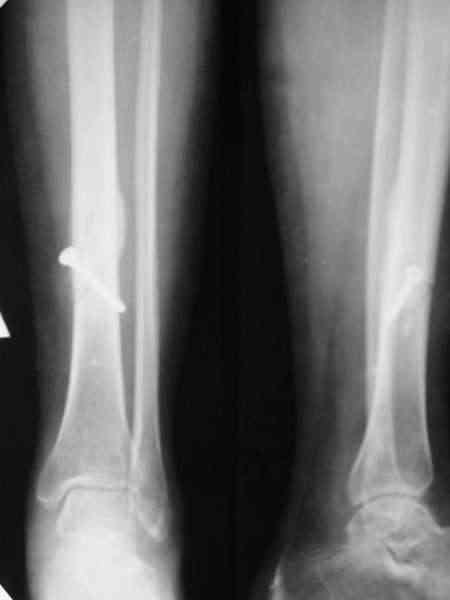

Типичный косо-спиральный перелом голени с низкой энергией, большеберцовая внизу, а сверху малоберцовая, и применение интрафрагментарного компрессионного шурупа можно оправдать, когда для

фиксации перелома выбран метод открытой фиксации пластинами, где пластина после стабилизации и компрессии перелома действует как нейтрализующая сила.

Из-за убедительных преимуществ перед другими методами, при лечении закрытых диафизарных переломов голени “золотым стандартом” считается применения метода закрытой репозиции с фиксацией интрамедуллярным штифтом, проксимальным и дистальным блокированием. Тенденция сегодняшнего дня - это перевод в окончательную фазу фиксации, в

Комбинированные: закрытая репозиция с перкутанной фиксацией и дополнительный наружный фиксатор, подходит к принципам “minimum implant, maximum benefit”, но такой метод приемлем, когда имеется желание минимизировать вмешательство из-за общего системного состояния, сосудистого-неврологического характера или диабет.

Метод также приемлем у больных для фиксации суставных фрагментов при внутрисуставных переломах и больным с политравмой, по причине того, когда больной не имеет возможности ранней нагрузки на эту конечность из-за наличия повреждения с этой же стороны, ацетабулума, внутрисуставных переломов коленного и голеностопных суставов или переломы пяточных костей.

Из-за механической слабости конструкции, хронические нежелательные микродвижения осложнялиись инфцированием фокуса травмы, переводили перелом из разряда банальных в сложные, где были нужны дополнительные восстановительные методы и метод был оставлен в начале 90х ортопедами.